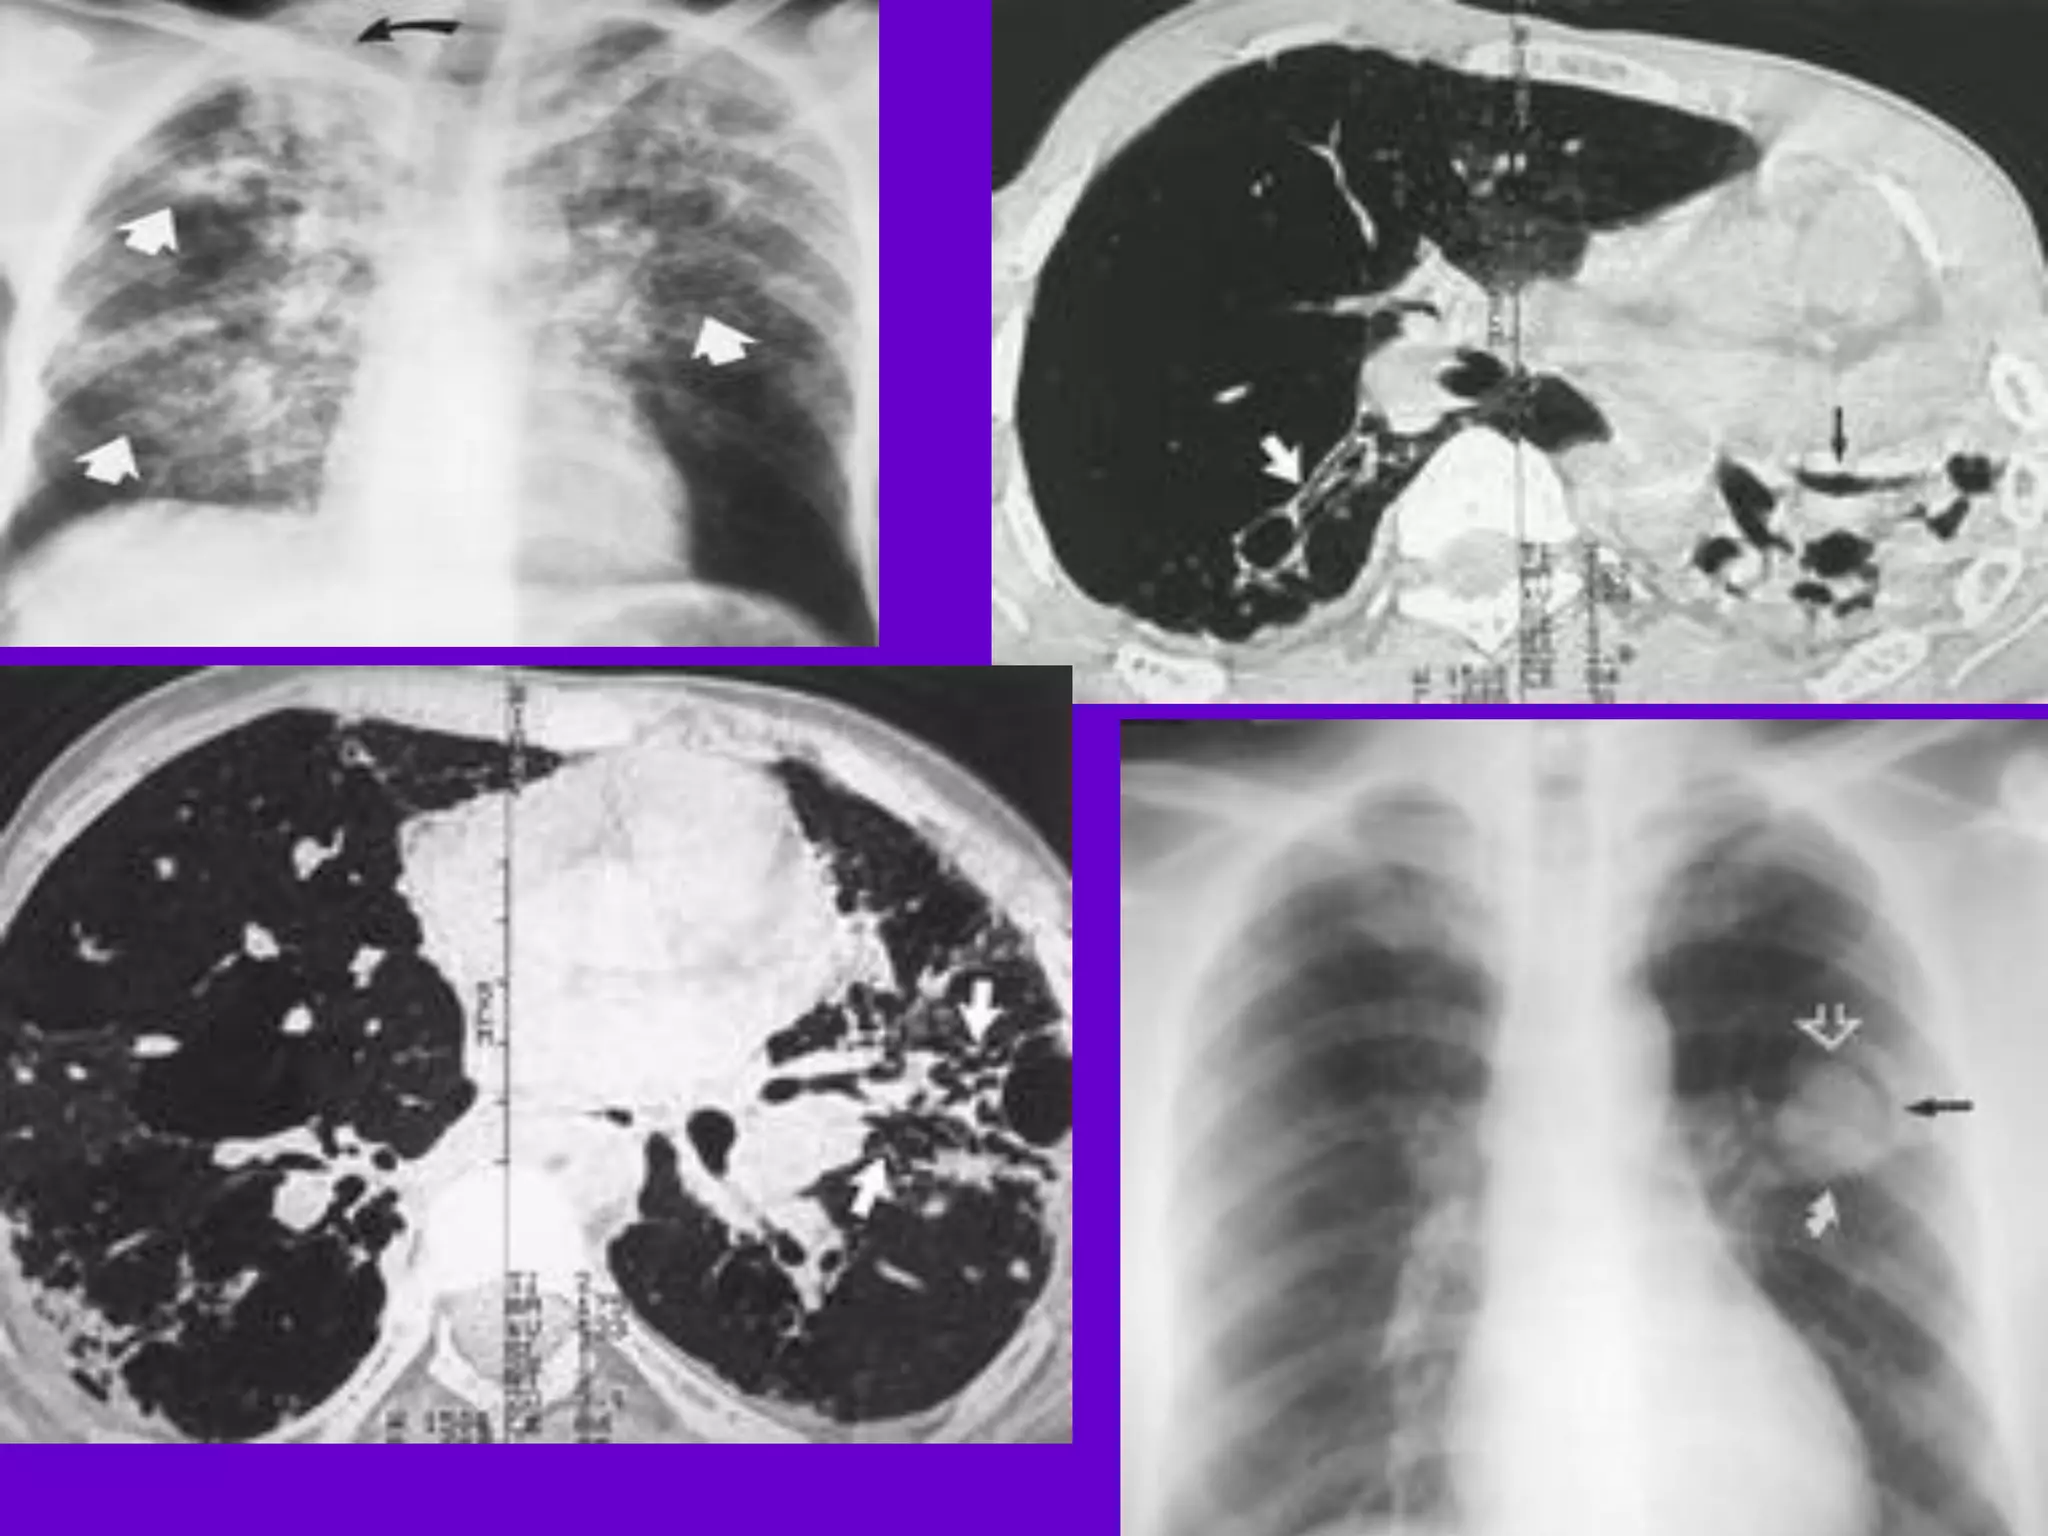

Miliary TB

􀂄 Earliest form of miliary TB is detectable

on HRCT.

􀂄 Coalescing nodules result into patchy

irregular

opacities and HRCT shows this variation

effectively

and has been described as “snowstorm

appearance”.

􀂄 HRCT shows cavitation, which is not

evident on plain

CXR.

Radiology:

1. Bilateral upper zone fibrotic shadows: with

shift of trachea, mediastinum, distortion of

fissures and diaphragm, and elevation of the

pulmonary hila.

2. Soft confluent shadows of exudative lesion

(D.D pneumonia)

3 Calcification.

4. Cavitation.

5. Tuberculoma.

6. Hilar and paratracheal lymph node

enlargement may be present.

Radiological classification:

1.Minimal: slight or moderate opacity. No

cavity. Extent not more than space

above 2nd costocondral junction.

2. Moderately advanced: In one or both

lungs. slight or moderate opacity, extent

equivalent to volume of one lung. Dense

confluent shadow equivalent to one third

the volume of one lung. Diameter of

cavities not more than 4 cm.

3. Far advanced:

Any lesion>the moderately advanced.

Miliary Tuberculosis

Produced by acute dissemination of tubercle

bacilli via the blood stream.The term miliary

derives from the radiological picture of

diffuse, discrete nodular shadows about the

size of millet seed (2mm).